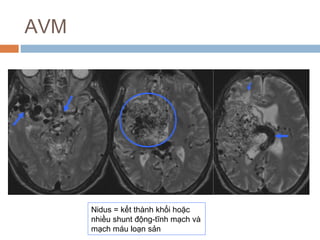

AVM

Nidus = kết thành khối hoặc

nhiều shunt động-tĩnh mạch và

mạch máu loạn sản